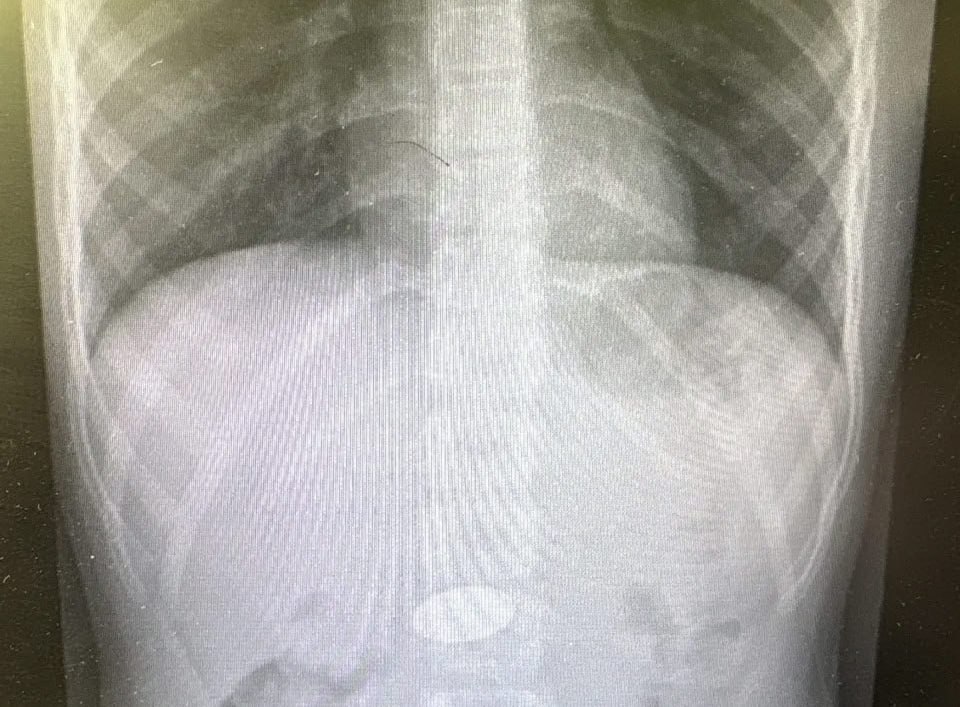

В Волгограде спасли мальчика, проглотившего пятирублевую монету

Ребенок был доставлен в детское хирургическое отделение клинической больницы №7. Мальчика уже выписали.